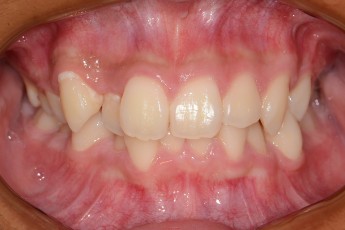

BEFORE & AFTER

- 덧니교정